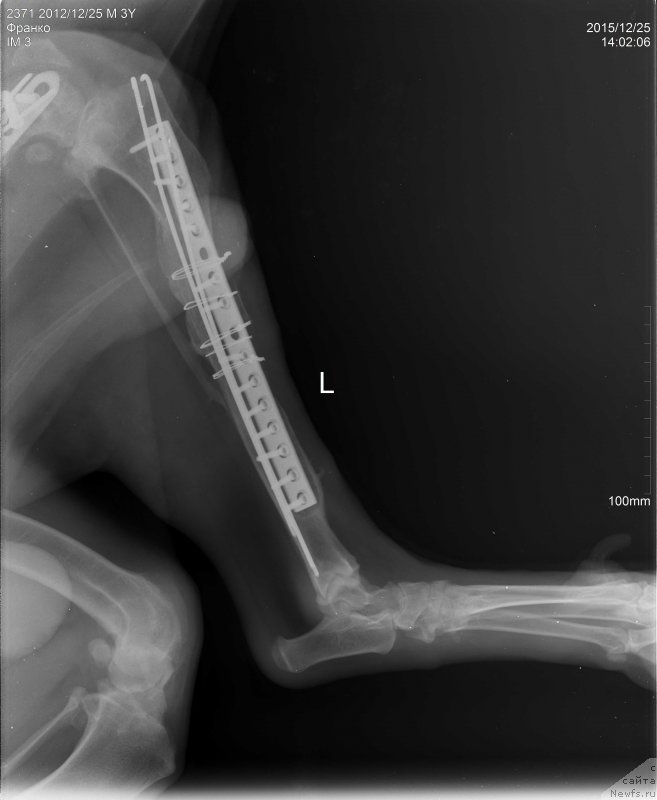

2015.12.25.=Франко снимки бедро латер

Фотография № 198290

2015.12.25.=Франко снимки голень

Фотография № 198291

2015.12.25.=Франко снимки таз ВД

Фотография № 198292

Сергей Александрович написал что абсцесс в мягких тканях а не в надкостнице, как нам озвучили на рентгене.

Ну и артроз коленного сустава.

Пластину на голени надо удалять.

Артроз у Франко ужаснейший.

Хуже мне кажется уже и быть не может.

Ноги Франко так устроены, что он сам их разбивает.

Это чудо , что он еще на ногах,

Нужно чтоб пластины стояли как можно дольше.

Чудо, что Франко на ногах, радуйтесь каждому месяцу.

Это нам написала наша врач.